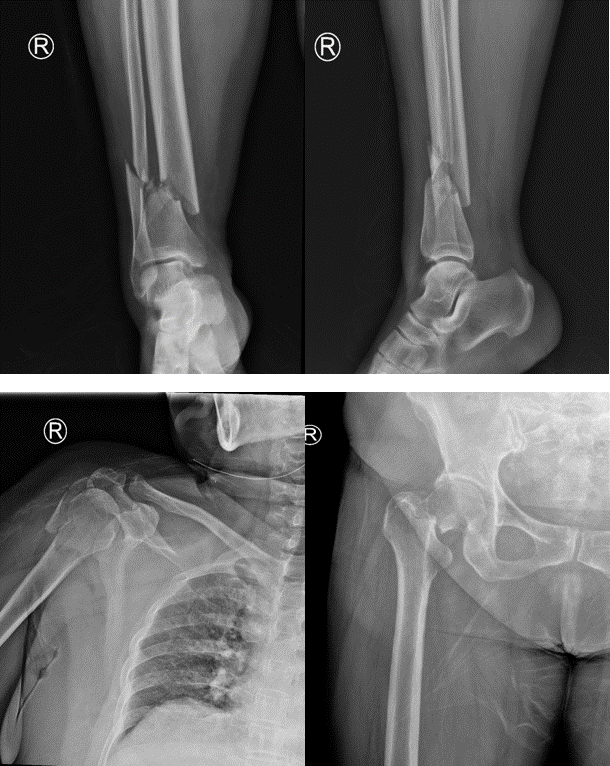

老家安徽的陈女士在苏州工业园区已经生活了很多年,一年前不幸遭遇车祸,当时短暂昏迷,全身疼痛无法活动,右侧耳还伴有出血。送至我院急诊后,诊断为:脑挫裂伤、肺挫伤、颅骨骨折、右侧上下肢骨折、右侧多根肋骨骨折,遂将患者收住重症监护室进行抢救治疗。

骨折X线

病情稍有稳定后,其它治疗迫在眉睫,如不能抓紧手术,严重的并发症将使患者再次陷入危险之中。骨科何罕亮副主任医师综合考虑患者情况,决定实施分期手术。第一次先行肱骨骨折切开复位内固定术 +胫腓骨骨折切开复位内固定术,第二次视患者情况择期行全髋关节置换术。